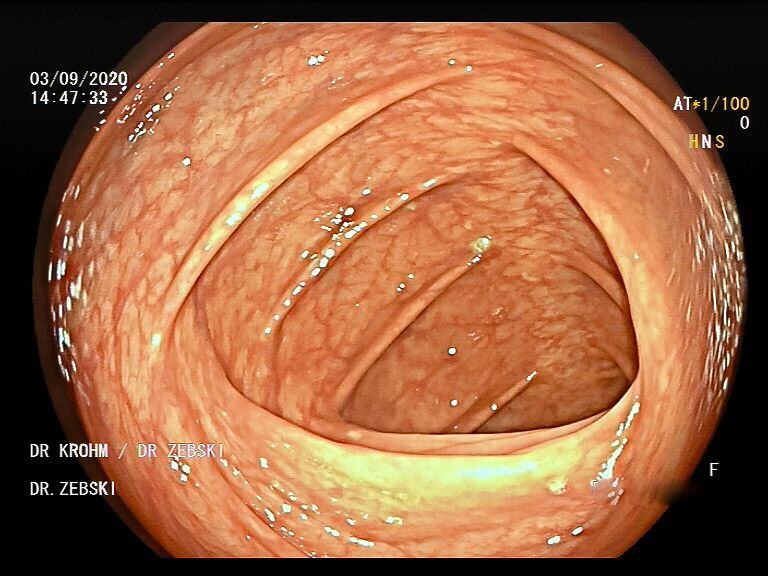

Die Darmspiegelung ist der uneingeschränkte Goldstandard für die Diagnostik und Vorsorge sämtlicher Erkrankungen des Dickdarms und des untersten Dünndarms. Die hochauflösende Bildqualität (High Definition) unserer modernen Videokoloskope ermöglicht eine zuverlässige Einordnung nahezu sämtlicher entzündlicher oder geschwulstiger Veränderungen der Dickdarmschleimhaut.